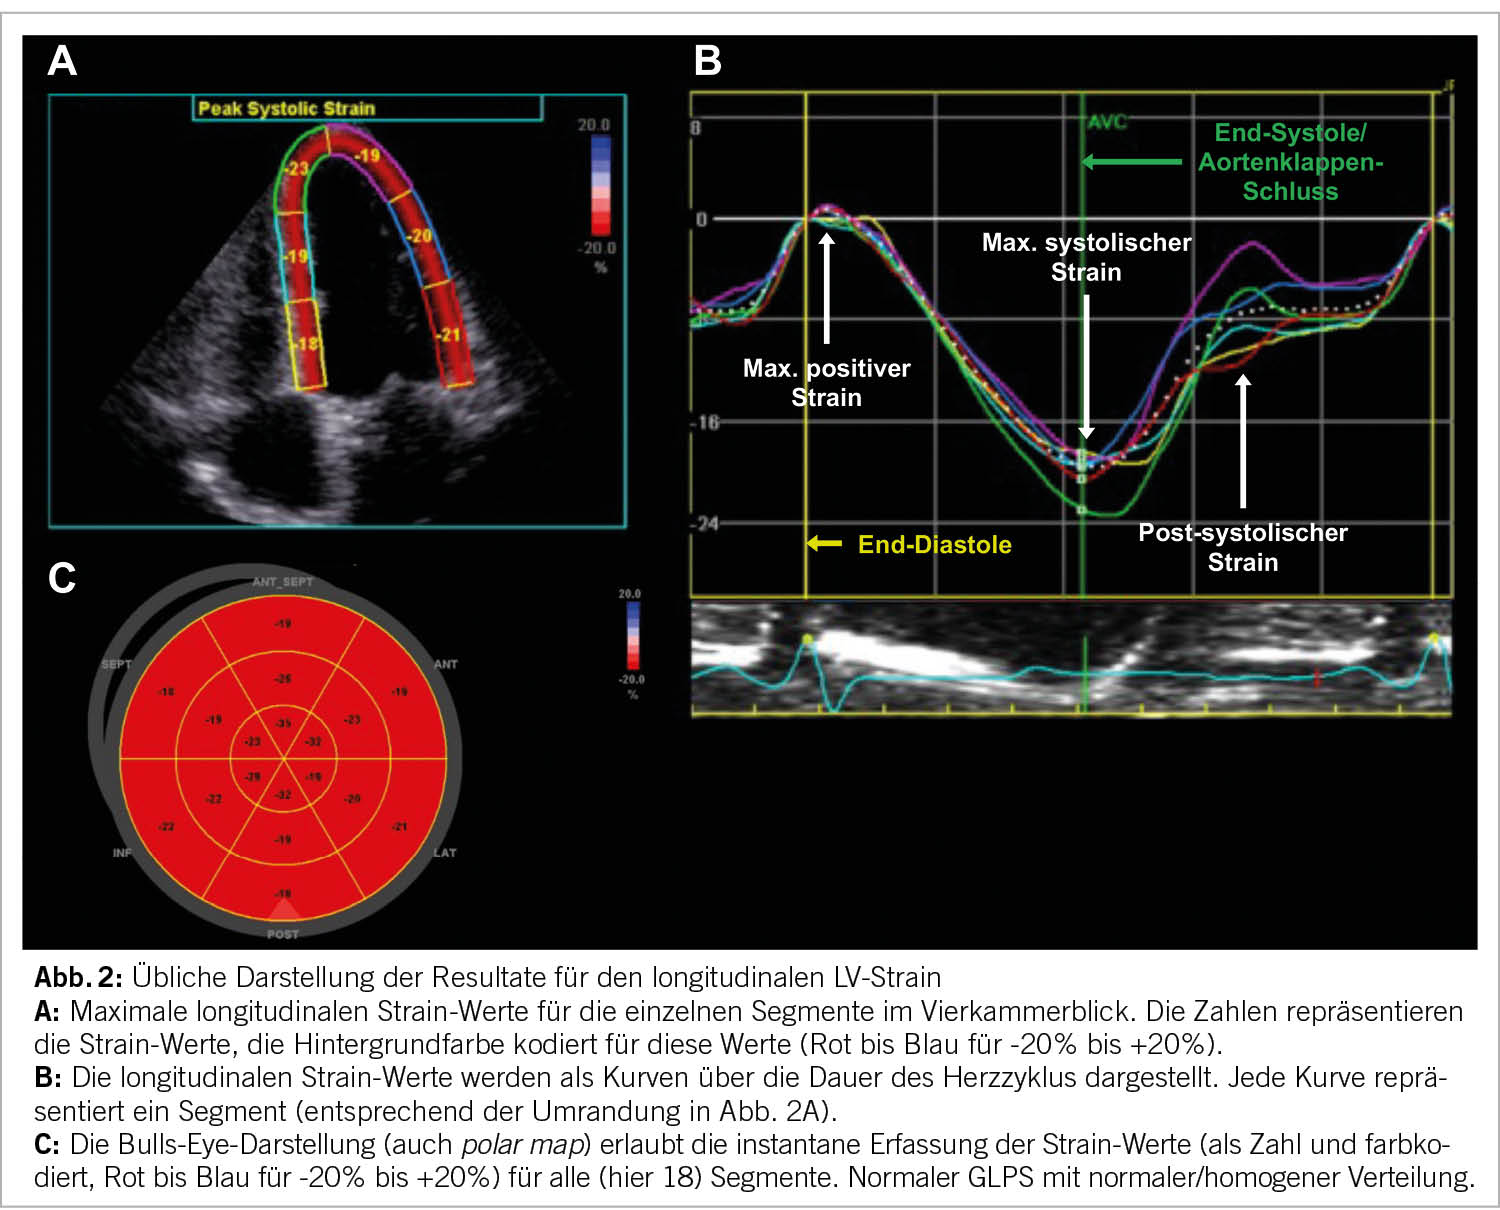

Nun wählt man die drei gewünschten Loops aus. Die neuesten Software-Versionen sind teilweise in der Lage, selbständig die korrekten Schnitte zu erkennen und die technisch geeignetsten auszuwählen. Nun wird die Software gestartet und der Algorithmus detektiert die Endokardgrenzen selbständig und legt die ROI auf das LV-Myokard. Anschliessend ist es wichtig, die korrekte Lage und auch Breite der ROI zu überprüfen und gegebenenfalls im Jojo-Modus (automatische, zeitliche Oszillation, welche die visuelle Erkennung des Endokards vereinfacht) anzupassen. Hier ist es wichtig, darauf zu achten, dass das Perikard nicht innerhalb der ROI liegt, da dieses naturgemäss keine Deformation zeigt und daher zu falsch tiefen Werten führen kann. Die Software teilt nun visuell und rechnerisch das Myokard in ein 17-Segement-Modell (teilweise auch 16 oder 18 Segmente) ein und liefert Werte für die einzelnen Segmente und Mittelwerte für das gesamte Myokard. Klinisch am etabliertesten ist dabei der GLPS, welcher den Mittelwert für die maximale, longitudinale, systolische Deformation in allen Segmenten beschreibt. Es ist möglich, einzelne Segmente von der Analyse auszuschliessen, falls die Bildqualität dort keine verlässliche Analyse zulässt. Üblicherweise werden die Ergebnisse visuell als Werte und farbcodiert in den einzelnen Segmenten der ROI angezeigt (Abb. 2A). Weitaus mehr Information liefert das Diagramm der Strain-Werte über die Dauer des Herzzyklus, dargestellt mittels einer Kurve für jeweils jedes einzelne Segment (Abbildung 2B). Zusätzlich und am anschaulichsten wird das Resultat in einer sogenannten Bulls-Eye-Darstellung (oder polar map) dargestellt, bei der alle einzelnen Segmente in einer einzigen Ansicht ersichtlich sind (Abb. 2C). Hierbei ist insbesondere die farbliche Darstellung der Maximalwerte hilfreich, die eine instantane qualitative Beurteilung zulassen (Rot für negative, Weiss für neutrale und Blau für positive Werte).

Eine dunkelrote Färbung signalisiert also eine starke systolische longitudinale Verkürzung (Kontraktion), eine blaue eine systolische Verlängerung des Segmentes (Dilatation, Dyskinesie). Anstelle der maximalen Strain-Werte können auch die Strain-Rate oder die Zeit bis zur maximalen Kontraktion angezeigt werden.